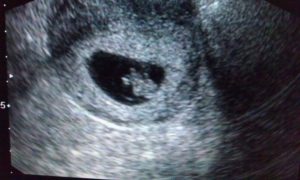

Узи 6 недель беременности

Узи 6 недель беременности: все, что сейчас можно увидеть на экране – это небольшое пятнышко, длина эмбриона – около 8 мм. Сердце уже прослушивается